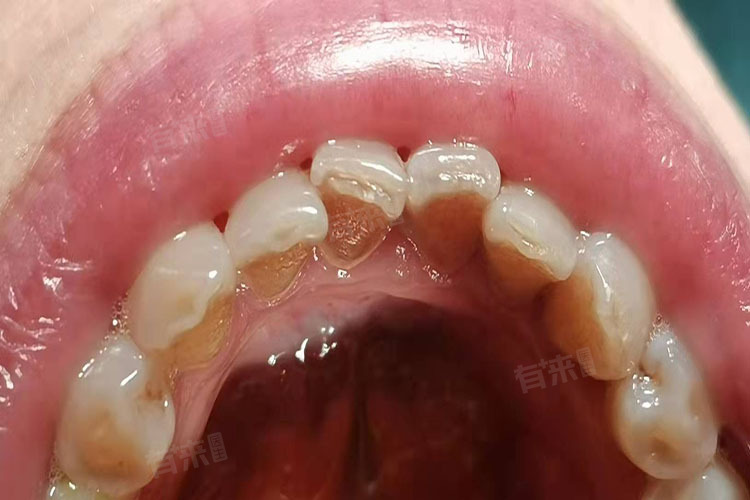

牙结石是在牙齿或修复体表面上出现的坚硬的黄色斑点,通常是由食物残渣、坏死的上皮细胞、细菌、无机盐等物质沉积钙化而成。形成原因包括口腔卫生习惯不佳、牙齿排列不整齐等,可以通过超声清洁、喷砂清除等方法改善。

- 牙齿排列不整齐:如果牙齿排列不整齐或牙齿表面比较粗糙,牙结石可能会比较容易沉积,增加患病的几率。

- 不良修复体:如果患者口腔内有不良修复体,如残根、残冠,尤其是后牙区的残根、残冠等,容易出现食物残渣沉积,且不易清理,长期以往可能会形成口腔结石。